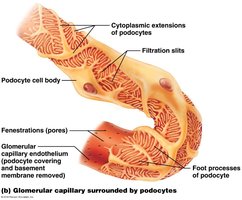

Renal Corpuscle: Includes the glomerulus (fenestrated capillary bed) and Bowman’s capsule (with podocytes forming filtration slits).

The filtration membrane consists of three layers: fenestrated endothelium, basement membrane, and podocyte filtration slits. It allows passage of water, ions, glucose, amino acids, and small proteins, but restricts blood cells and large proteins.